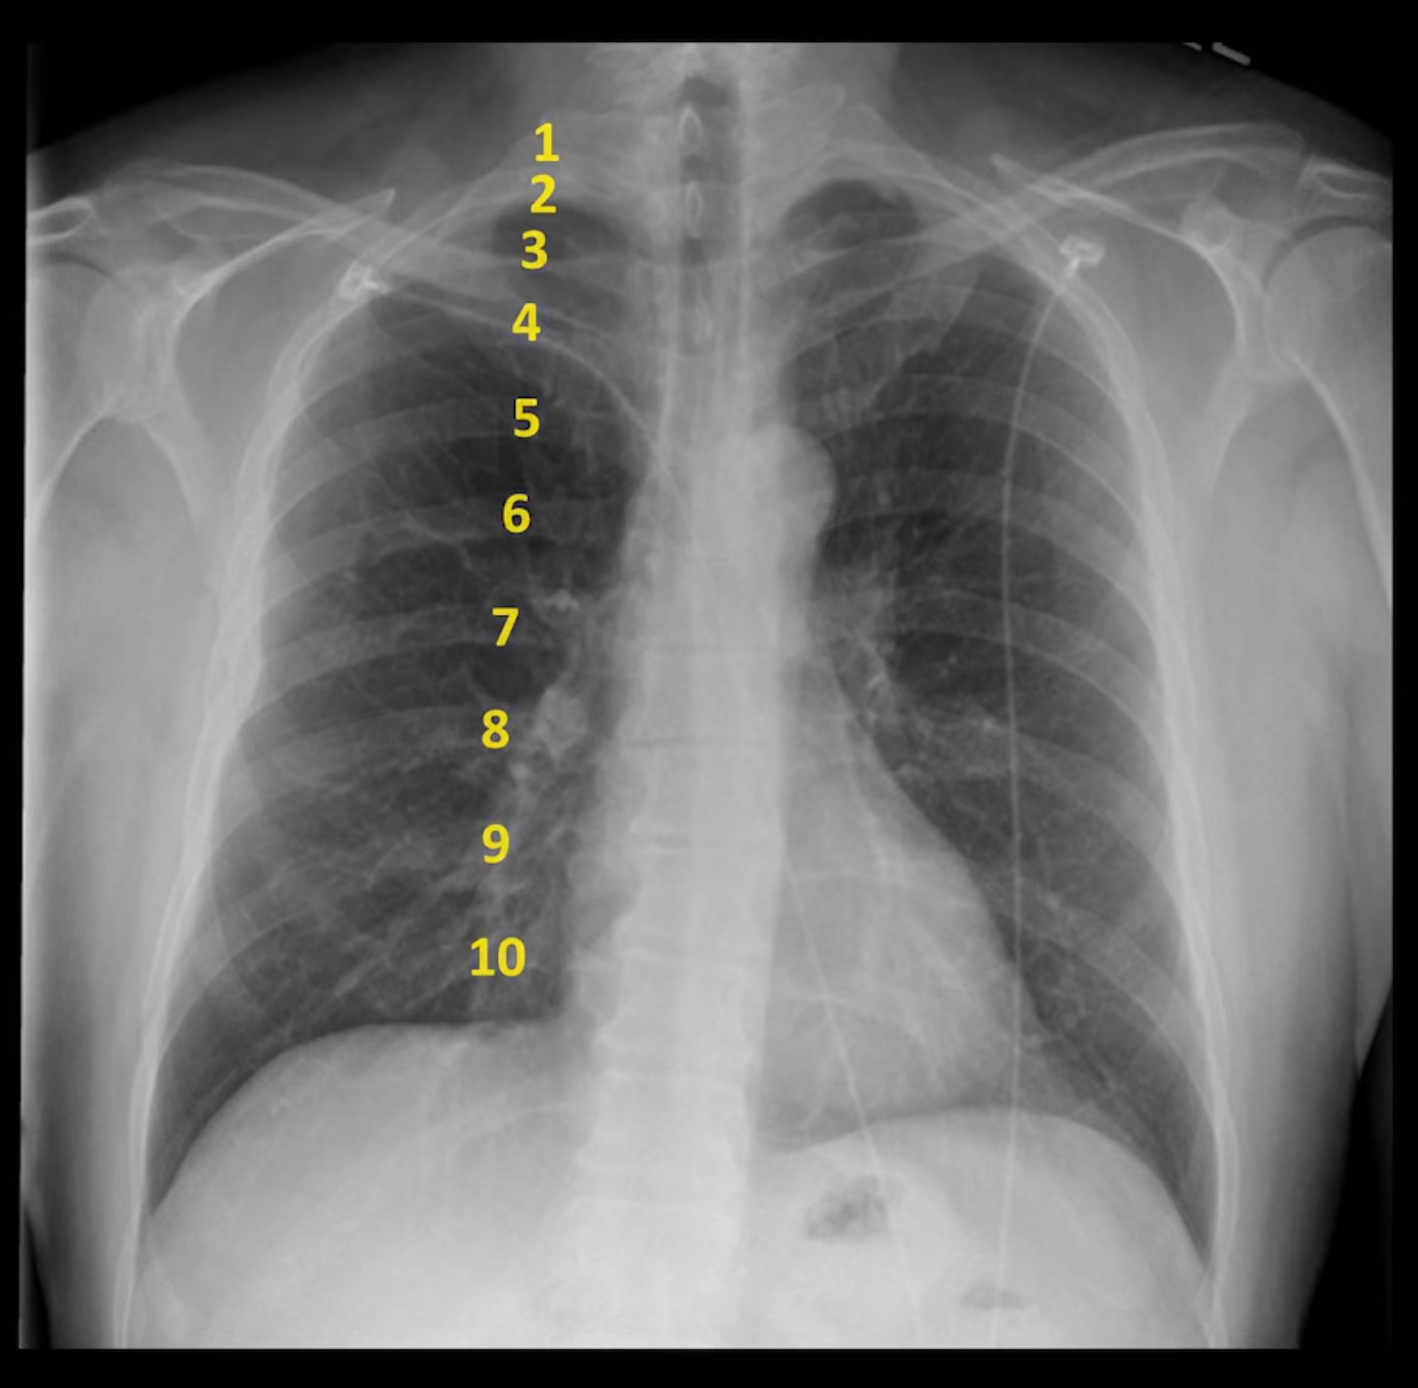

Diffuse Lung Volume Processes

Reduced Lung Volume

Defined as <9 posterior ribs. Can be due to: poor inspiratory effort, suboptimally timed exposure, restrictive lung disease, subpulmonic effusions.

Hyperinflation